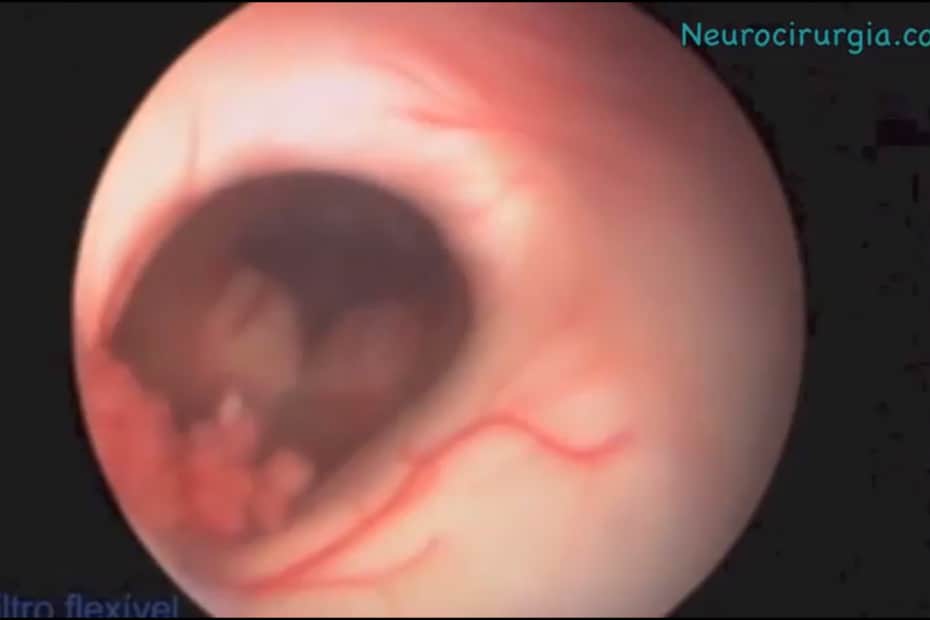

Endoscopia Cerebral – Cisto Colóide

Cistos colóides são lesões benignas que constituem cerca de 1% de todos os tumores intracranianos. Tipicamente estão localizados nos ventrículos cerebrais, que são bolsões onde… Read More »Endoscopia Cerebral – Cisto Colóide